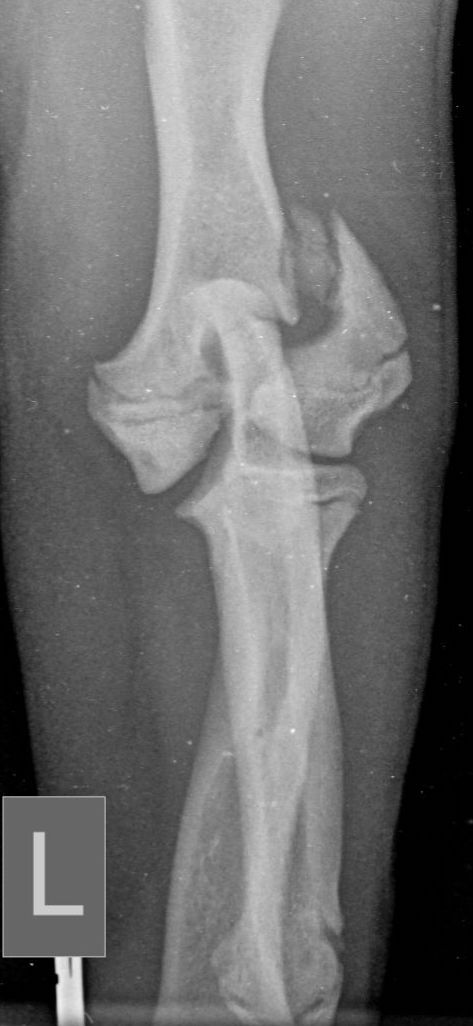

Traditionally, humeral unicondylar (lateral or medial) fractures have been managed with internal fixation using a transcondylar bone screw and an anti-rotational device. This is generally a Kirschner wire (K-wire) or Steinmann pin (Figure 1), which is placed across the epicondylar ridge component of the fracture (Bojrab, 1975; Denny and Butterworth, 2000; Jackson, 1983; Olmstead, 1993). However, reports of complications relating to mechanical failure due to implant migration in a series of patients varying widely in age and breed concluded that using a supracondylar K-wire is more likely to cause major complications than using an epicondylar bone plate (Perry et al., 2015; Sanchez Villamil et al., 2019). This conclusion was endorsed by an in vitro study that showed that stiffness, yield load and load to failure are all greater when bone plates, rather than K-wires, are used in conjunction with a transcondylar bone screw to stabilise humeral unicondylar fractures (Coggleshall et al., 2017).

These concerns have led to recommendations being altered over the past decade or so, with veterinarians now using bone plates, instead of K-wires, as an adjunct to a transcondylar screw when managing humeral unicondylar fractures (Figure 2), even in puppies (Figure 3) (Clark, 2016; Kvale et al., 2022). However, the basis on which this conclusion for puppies was reached appears to have been flawed because it assumed that what had been shown to be the case for adults would also apply to immature patients. As the conclusion was felt to conflict with the author’s experience of treating such patients, a retrospective study was undertaken to evaluate complications and outcomes in immature dogs treated for humeral unicondylar fractures at one centre over a 10-year period (Butterworth, 2022). The findings of this study are summarised in this article.